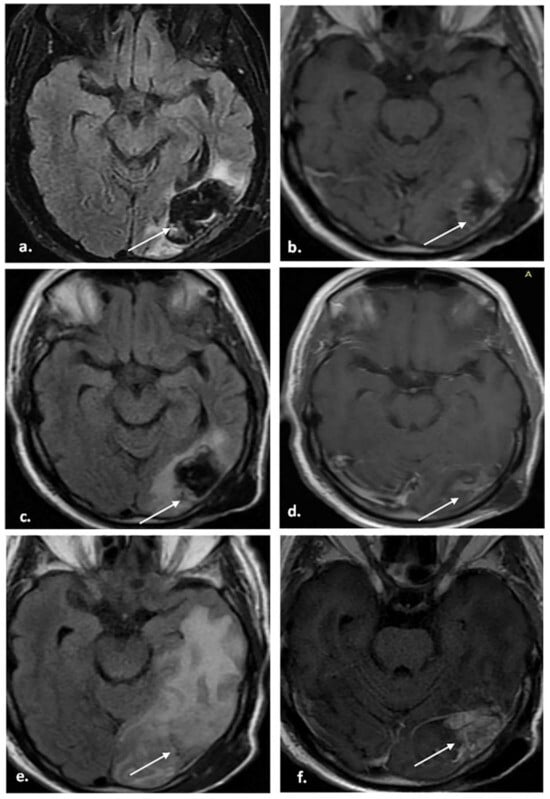

| Category | Description | Imaging Patterns | Management Recommendation |

|---|---|---|---|

| BT-RADS-0 | No score. | New baseline, incomplete study, or inability to categorize. | Continued follow-up, no change. |

| BT-RADS-1a | Improvement suspected due to a decrease in TP and/or treatment effects. Clinically stable or improved. | Reduction in enhancing component, FLAIR component, mass effect, or resolution of lesions compared with prior MRI. | Continued follow-up, no change. |

| BT-RADS-1b | Improvement potentially due to treatment effect. Clinically stable or improved. | Reduction in enhancing component, FLAIR component, mass effect, or resolution of lesions compared with prior MRI. | Continued follow-up, no change. |

| BT-RADS-2 | No significant change. Clinically stable. | No substantial change in enhancing component, FLAIR component, mass effect, or new lesions compared with prior MRI. | Continued follow-up, no change. |

| BT-RADS-3a | Worsening may represent the treatment effect. Clinically stable. | Mild increase (<25%) in enhancing component, FLAIR component, or mass effect compared with prior MRI. | Decreased time interval of follow-up. |

| BT-RADS-3b | Indeterminate. Worsening may be a mix of TP and treatment effects. Clinically stable. | Moderate increase in enhancing component, FLAIR component, mass effect, or new lesion compared with prior MRI. | Decreased time interval of follow-up. |

| BT-RADS-3c | Worsening favors TP. Clinically worsening. | Significant increase (>25%) in enhancing component, FLAIR component, mass effect, or definite new lesion compared with prior MRI. | Change in management vs. decreased time interval of follow-up. |

| BT-RADS-4 | Worsening, highly suspicious for TP. Clinically worsening. | Substantial increase in enhancing component, FLAIR component, mass effect, and/or multiple new lesions compared with prior MRI. | Change in management. |